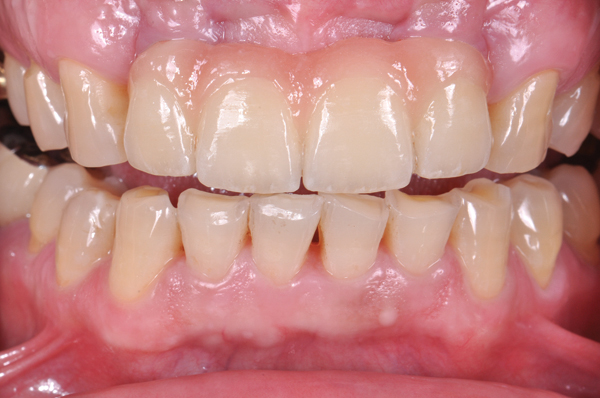

CL-IIIb high-strength 100% crystalline ceramics initially were alumina-based materials (eg, Procera®, Nobel Biocare, www.nobelbiocare.com); more recently they are zirconia-based (eg. LAVA™, 3M ESPE, www.3MESPE.com; Prettau®, Zirkonzahn, www.zirkonzahn.com). Alumina systems have proven successful for single units but are being replaced by zirconia and lithium disilicate due to the increased risk of failure in the molar region.25,26 Zirconia can also be used when significant tooth structure is missing, when high risk for flexure and stress is present, for posterior full-crown and fixed partial denture situations (Figure 13 and Figure 14), and when adhesive bonding is problematic, such as with subgingival margins.

Fig 13. Porcelain-layered zirconia framework (CL-IIIb) with layered pink porcelain for the gingiva (Fig 13); final image in the mouth of the porcelain-layered zirconia framework (Fig 14) (images courtesy of Aram Torosian, MDC).

Fig 14. Porcelain-layered zirconia framework (CL-IIIb) with layered pink porcelain for the gingiva (Fig 13); final image in the mouth of the porcelain-layered zirconia framework (Fig 14) (images courtesy of Aram Torosian, MDC).